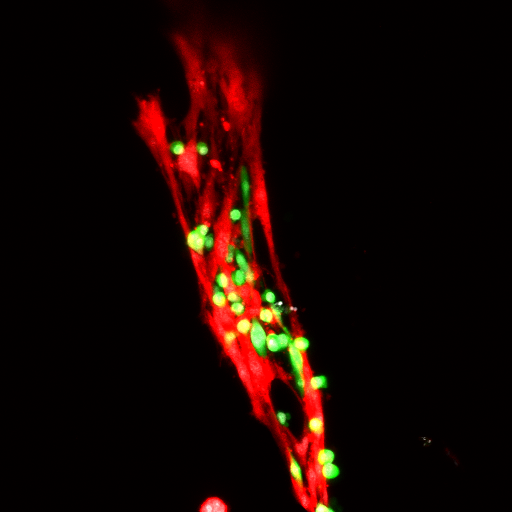

“Muscle satellite cells are resident stem cells in your skeletal muscles. They live on muscle strands like specks, and they’re key players in making new muscle tissue,” Han said.

“Our new hydrogel protects the stem cells, which multiply and thrive inside the matrix. The gel is applied to injured muscle, and the cells engraft onto the tissues and help them heal,” said Woojin Han, a postdoctoral researcher in Georgia Tech’s School of Mechanical Engineering and the paper’s first author.

“The stem cells keep multiplying and thriving in the gel after it is applied,” Jang said. “Then the hydrogel degrades and leaves behind the cells engrafted onto muscle tissue the way natural stem cells usually would be.”